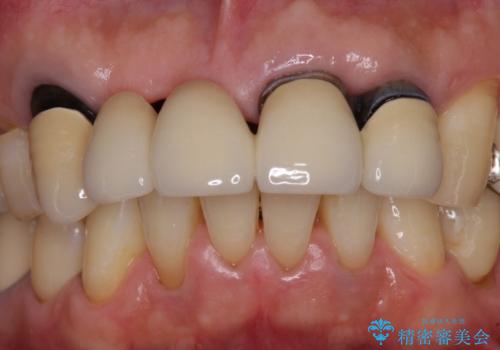

- 前歯のブリッジのせいで話しにくく、金属の縁などが露出して見栄えが悪いので、作り直したいとのことで来院された患者様です。

土台となる歯は根管治療の結果が良好ではないため、根管治療からやり直しをした後、オールセラミックブリッジにて補綴することとしました。